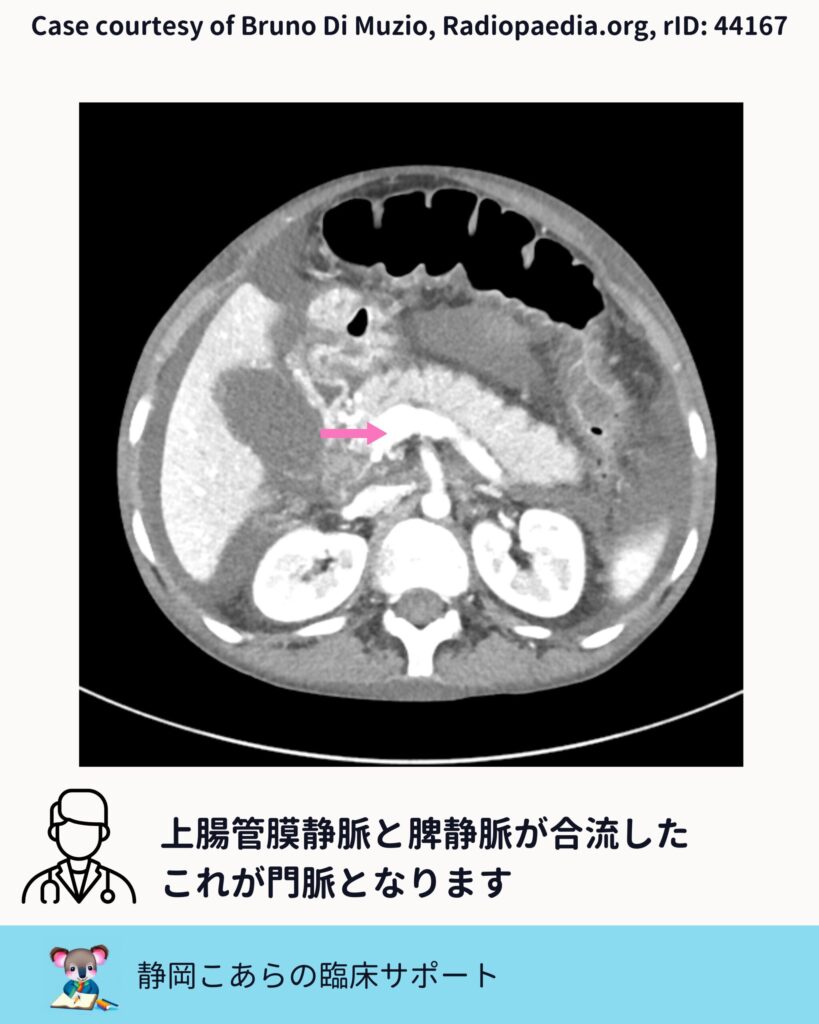

脾静脈との合流

次に確認するのが脾静脈です。膵の背側を水平に走る太めの静脈で、これもCTでは比較的見つけやすい構造です。

上腸間膜静脈と脾静脈。この二つが合流したところが、門脈になります。

ここまで来ると、「門脈を探す」のではなく、「合流点を確認する」という発想に変わります。探し物の精度が、一段上がる感覚です。